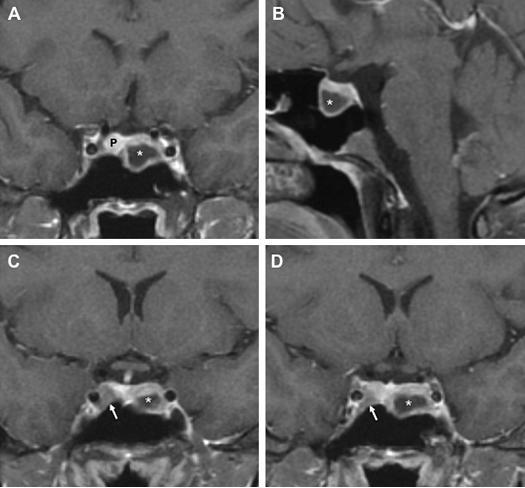

两类表型发生的概率相等,同源性表达同类垂体肿瘤,或是异质性的,发生不同类的垂体肿瘤。相对于散发性腺瘤来说,在异质性家系中,泌乳素腺瘤表现为侵袭性更强,发生于近鞍和海绵窦侵袭的概率更高。相反在同源性家系中,生长激素腺瘤的侵袭性更强。